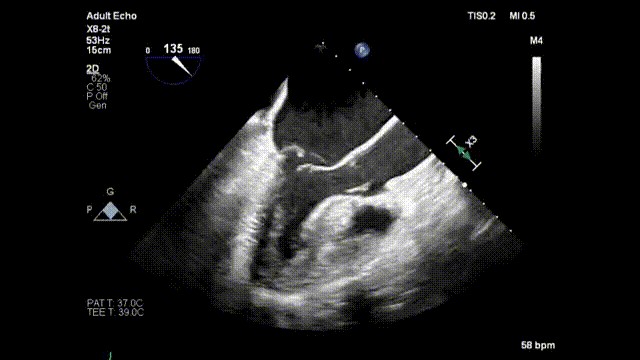

术前二尖瓣重度反流

术中器械顶住二尖瓣并击发,锚定人工腱索